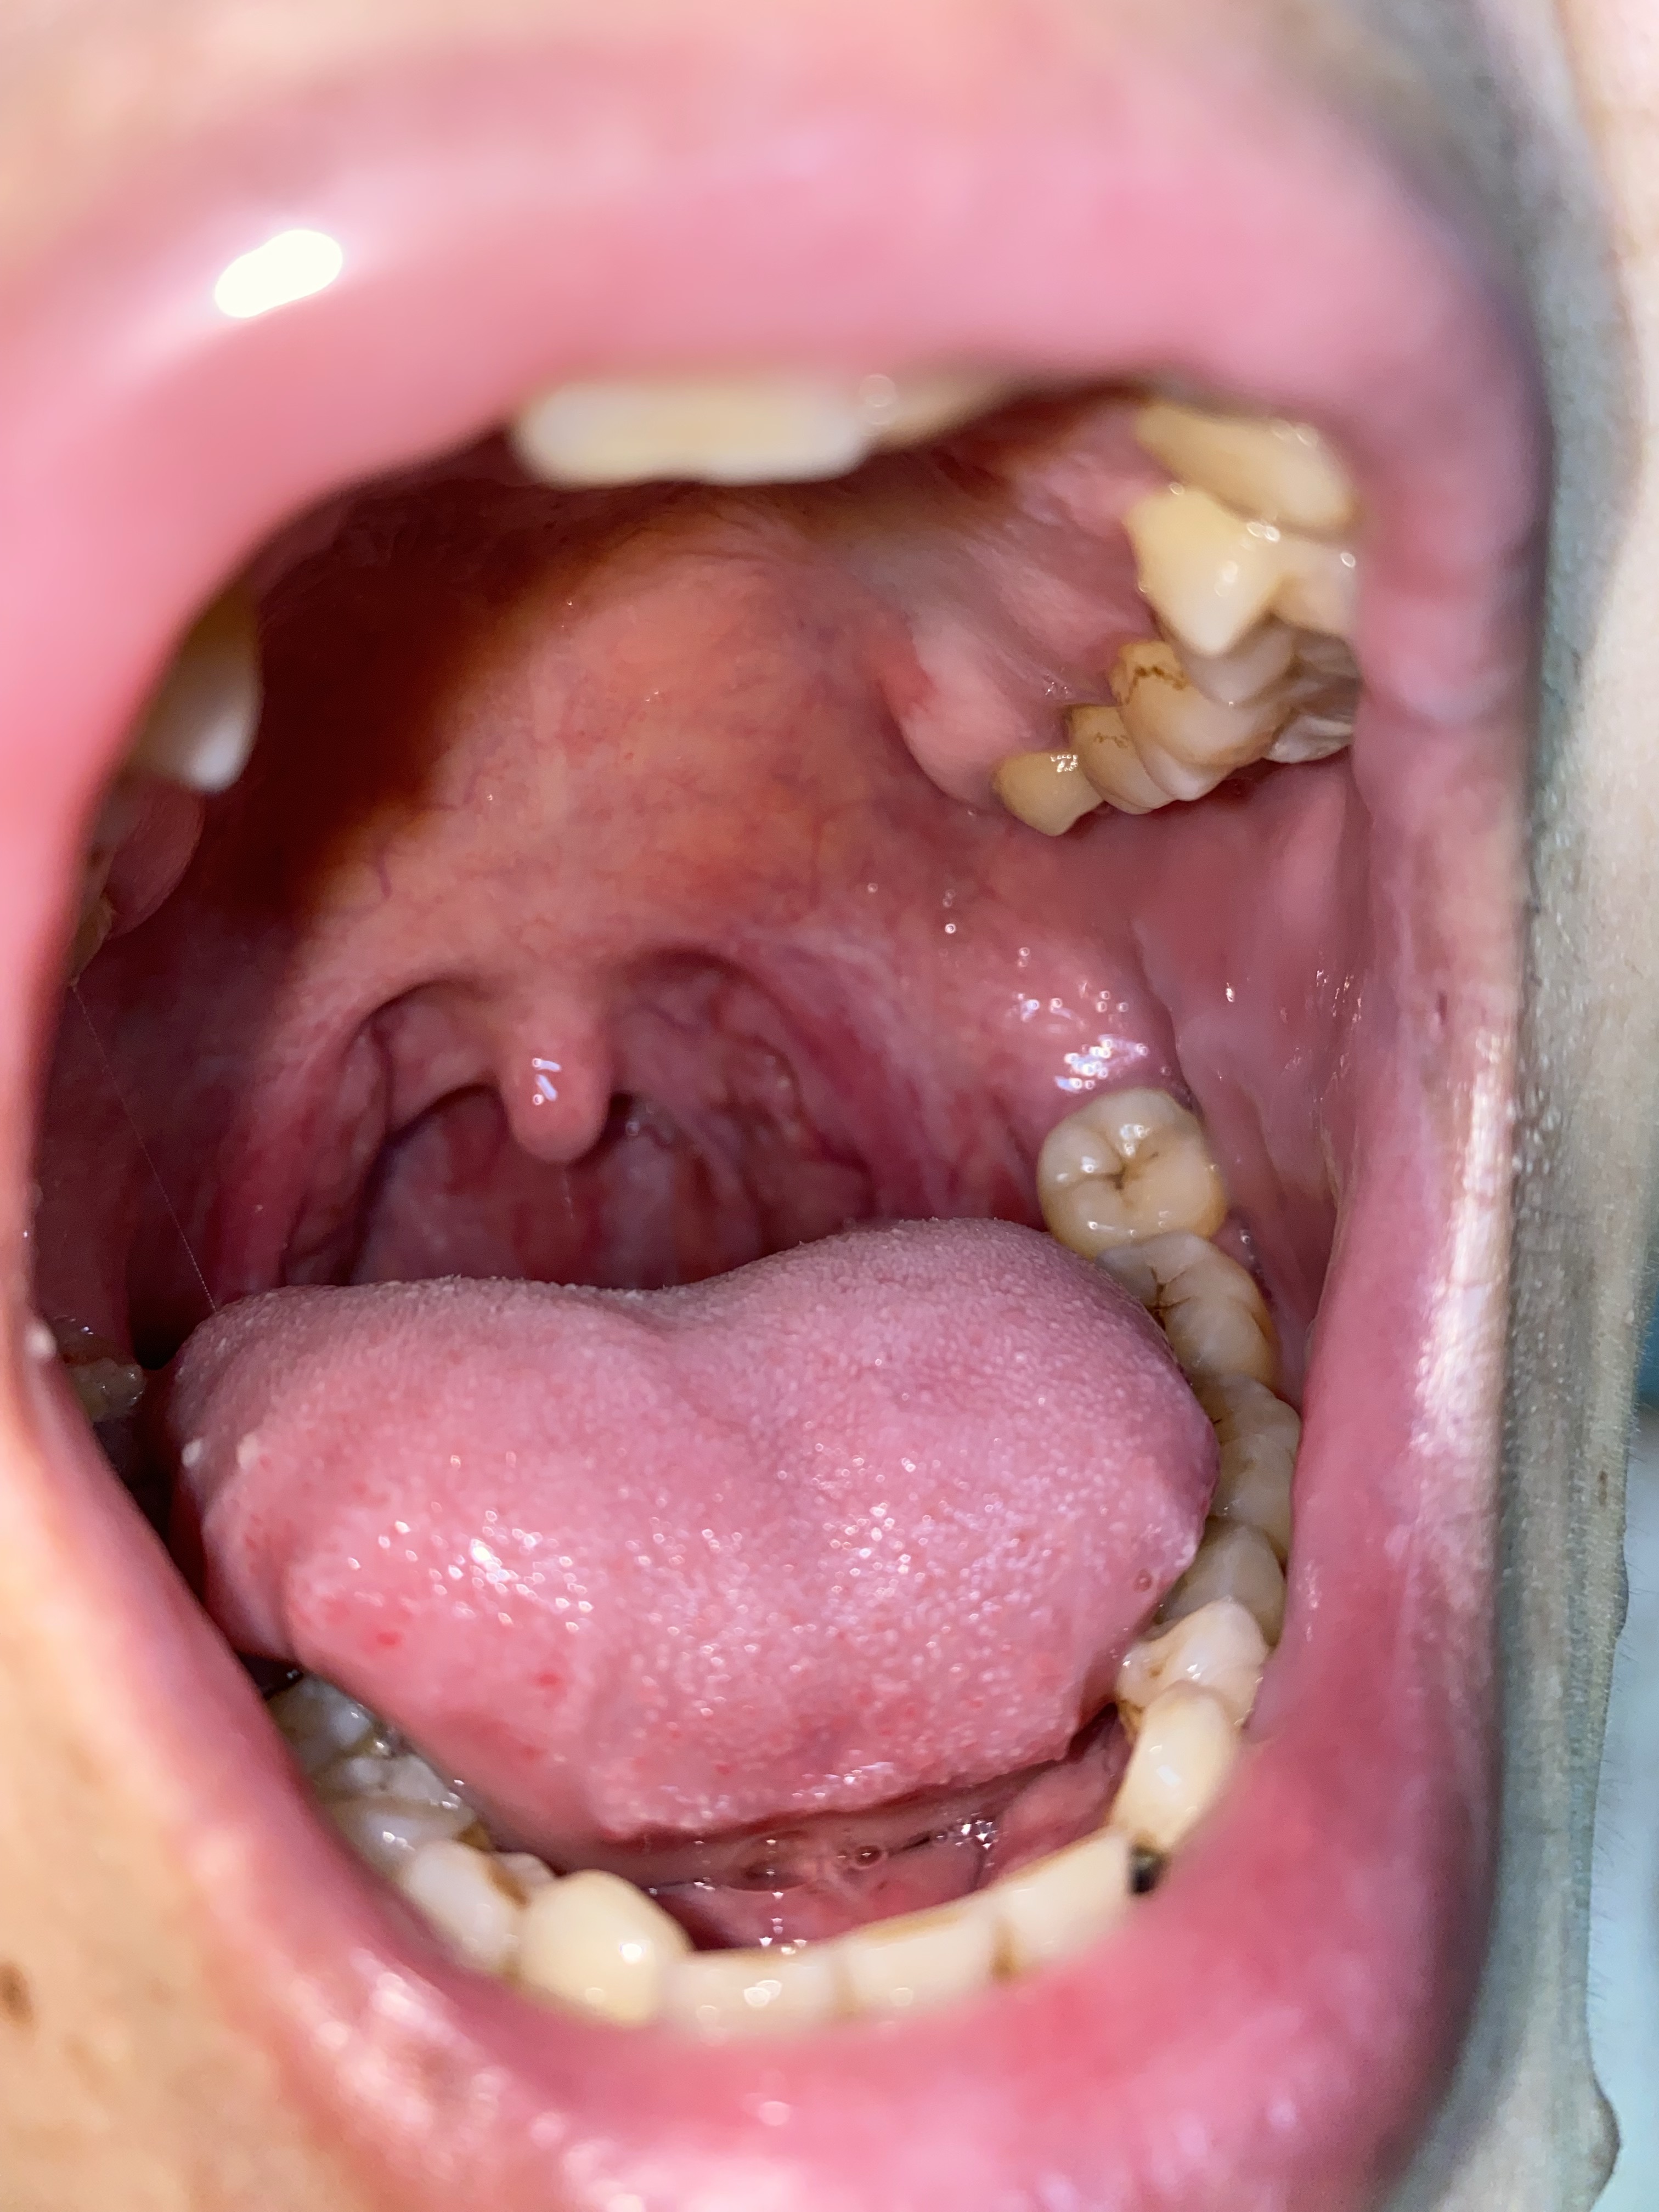

Họng có bị viêm abidan, hiện tại họng em nó bị lở loét chổ cục abidan, cảm giác đau khi ăn nhai, nuốc nước, mong bác sĩ chỉ dẩn hướng khắc phục ạ

Hiện tại anh dùng thuốc gì chưa.